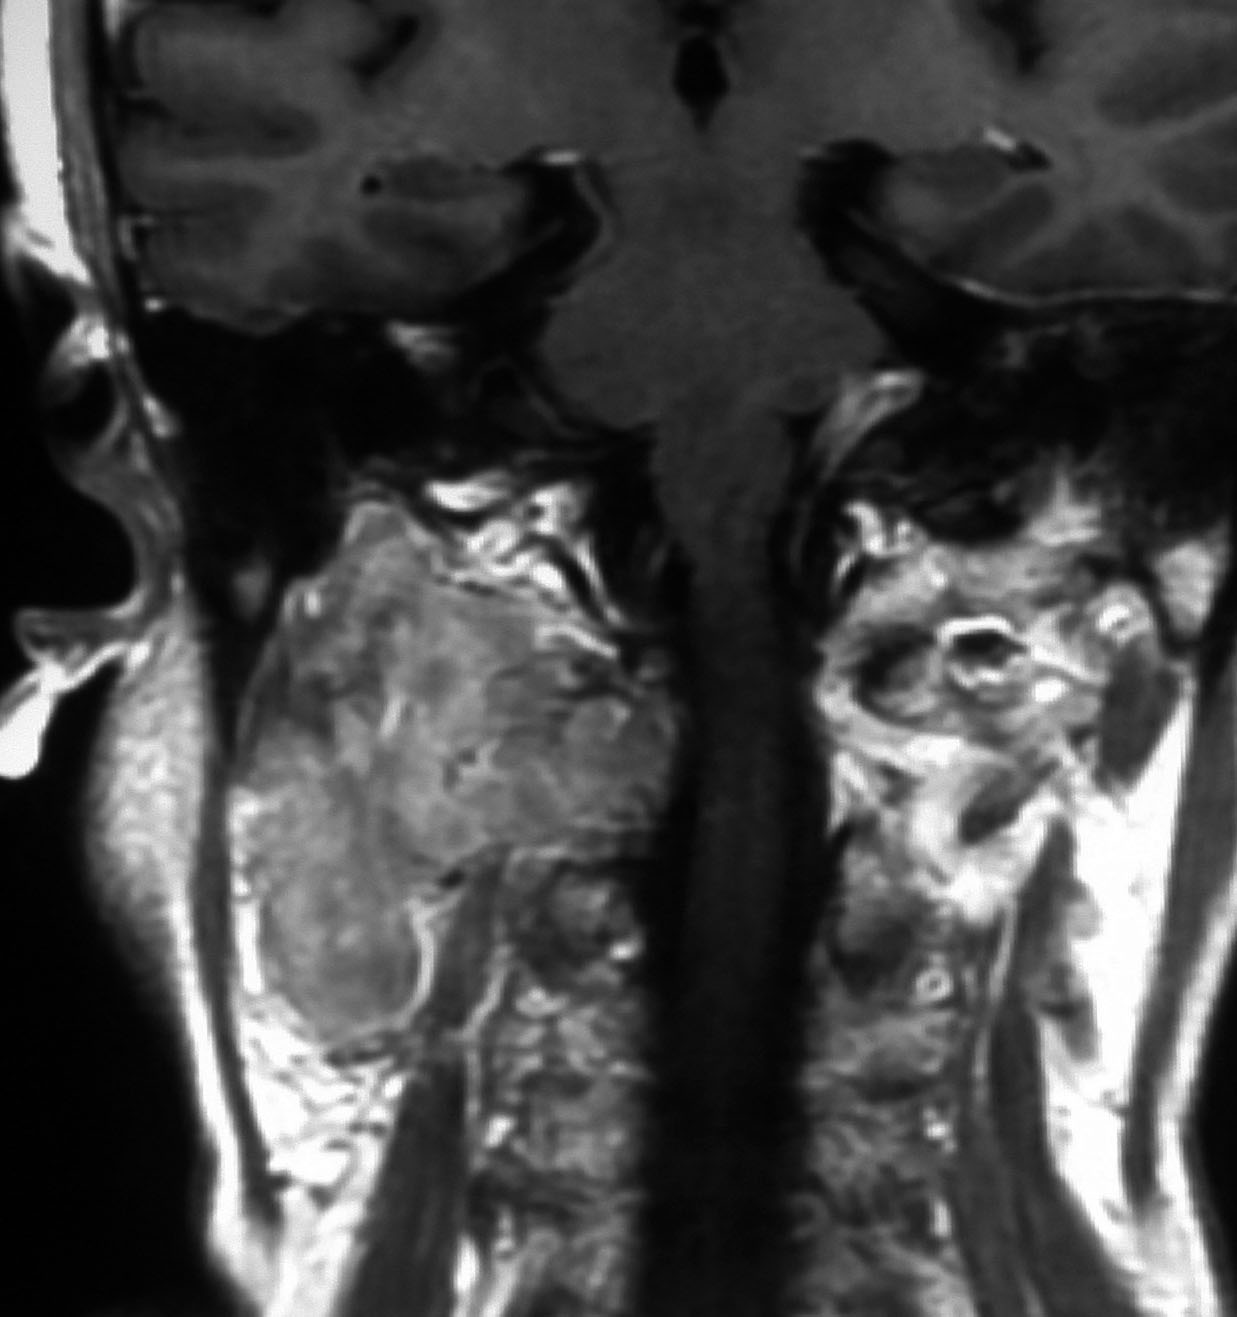

左は1991年,右は2006年のMRI画像です。15年間で腫瘍のサイズは変わっていません。

1991年に50代の女性にみつかったものでした。黄色に示したルートで摘出できないわけではありませんが,右後頭部が腫れてきたという訴えとホルネル症候,軟口蓋麻痺しかなかったので,何も治療しないでほっておきました。2016年まで25年間観察し続けました。症状の悪化は全くなく元気に暮らしておられます。グロームス腫瘍はある一定の年齢になると増大しないという性質を持っている良性腫瘍です。これを大々的な頭蓋底外科手術で摘出するするという愚を犯してはなりません。